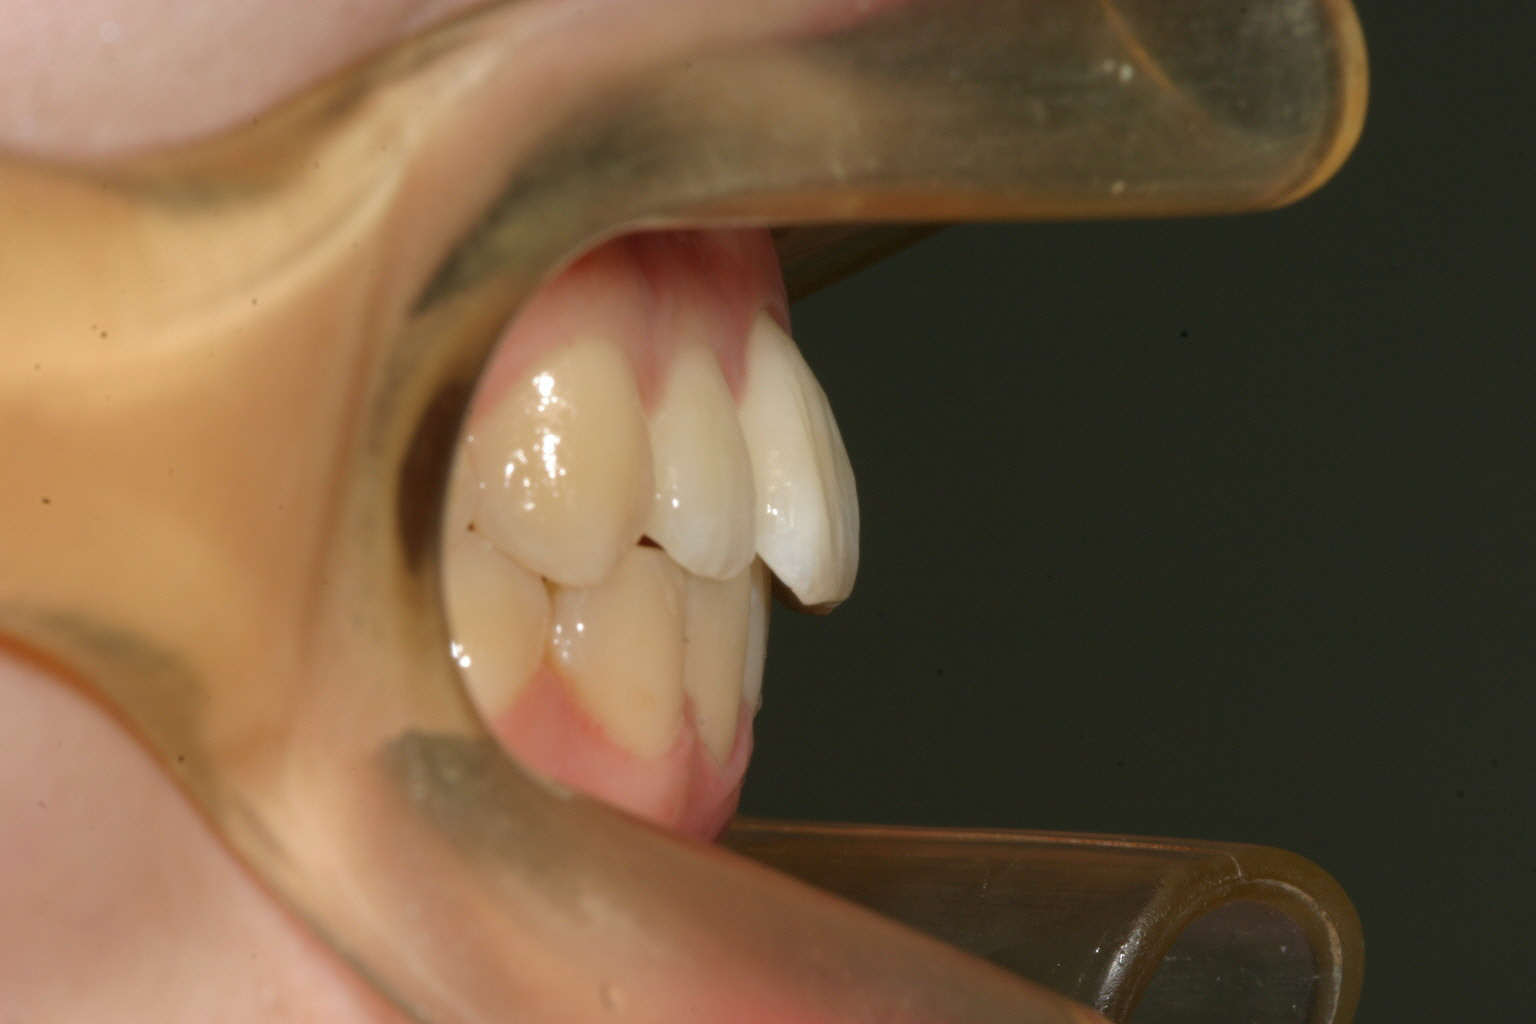

前突も改善しました。